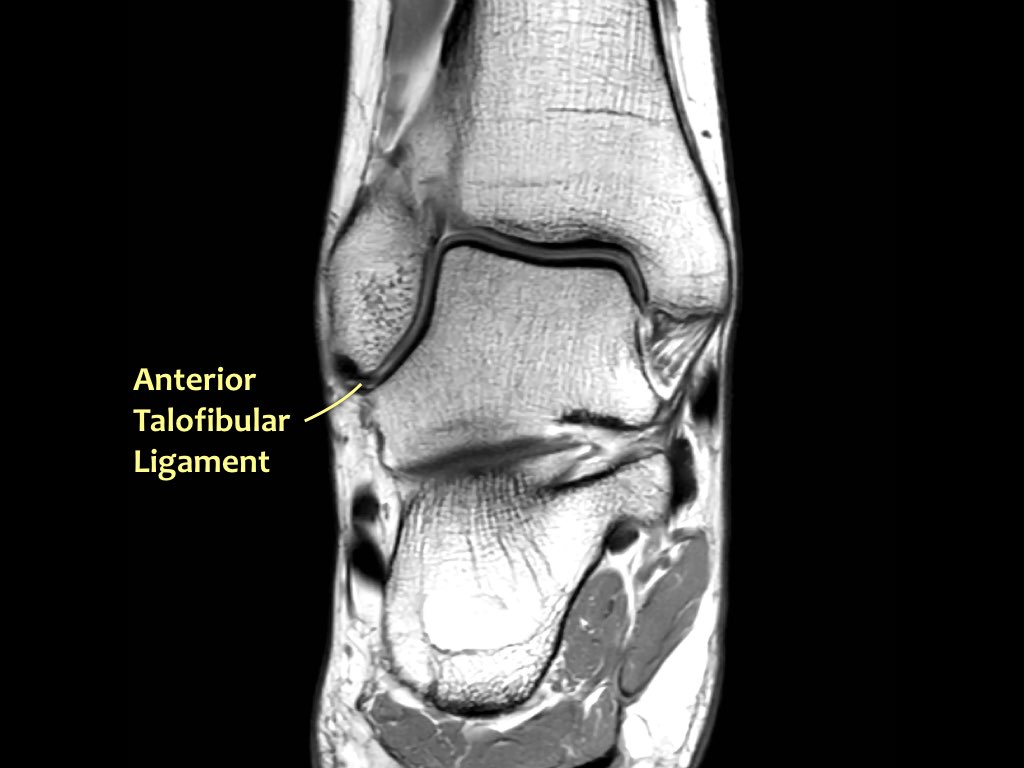

ATFL

Có ba dây chằng ở phía ngoài:

- Dây chằng sên mác trước (anterior talofibular ligament – ATFL)

- Dây chằng gót mác (calcaneofibular ligament – CFL)

- Dây chằng sên mác sau (posterior talofibular ligament – PTFL).

Dây chằng ATFL chạy từ mắt cá ngoài ra phía trước đến bờ ngoài của xương sên.

Dây chằng này có hướng nằm ngang và được quan sát rõ nhất trên ảnh cắt ngang.

Đây là dây chằng bị tổn thương thường gặp nhất ở cổ chân và cũng là dây chằng đầu tiên bị tổn thương ở phía ngoài.

Điều này có nghĩa là khi dây chằng CFL hoặc PTFL bị tổn thương, rất có khả năng dây chằng ATFL cũng đã bị tổn thương.

Cuộn qua các ảnh cắt vành.

Bạn có thể phóng to ảnh bằng cách nhấp vào.

Đây là hình ảnh của ba bệnh nhân có tổn thương dây chằng ATFL.

Bệnh nhân bên trái có phù nề nhẹ xung quanh dây chằng ATFL, trong khi bản thân dây chằng trông bình thường.

Đây có thể là căng dây chằng mức độ nhẹ (độ 1).

Thường được nhận thấy rõ nhất trên ảnh có kỹ thuật ức chế mỡ (fatsat).

Bệnh nhân ở giữa có dày lên và rối loạn cấu trúc, biểu hiện của rách một phần (độ 2).

Bệnh nhân bên phải có rách toàn bộ chiều dày (độ 3).